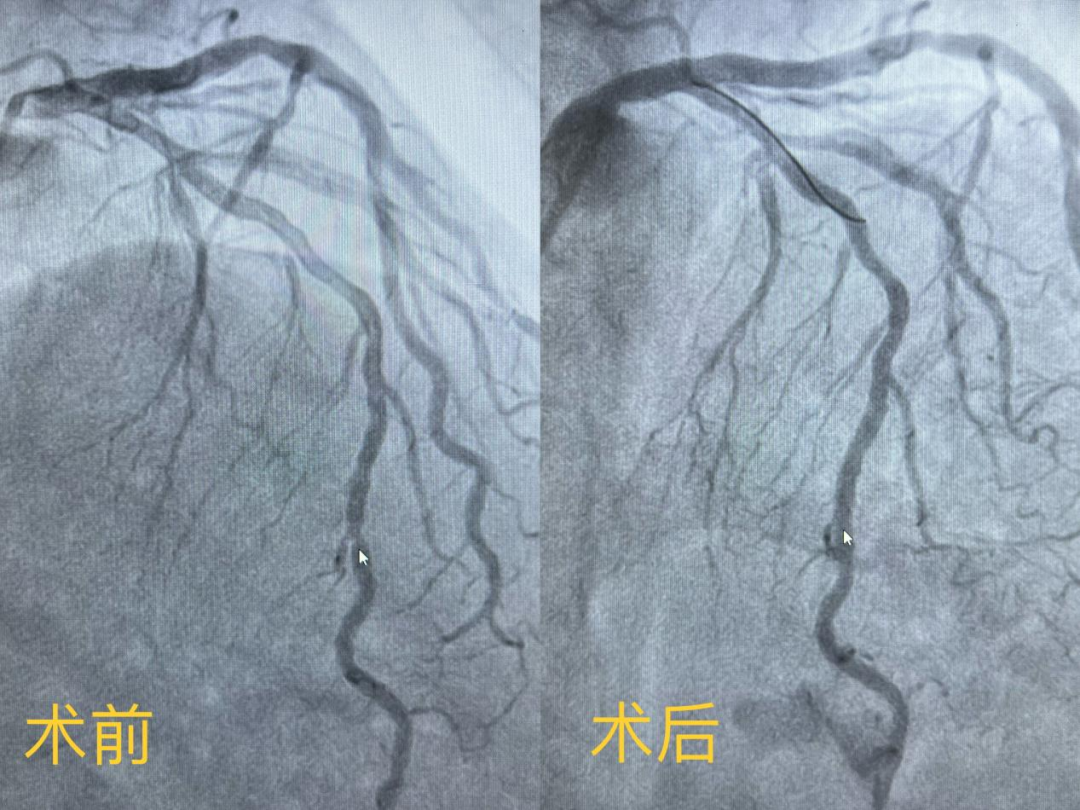

女性患者,因反復胸痛10余年就診我院,心內科團隊為其行冠狀動脈造影確診冠心病,左前降支遠段中部90%狹窄,需要行冠脈支架植入治療。在與患者及家屬溝通時,患者家屬提到,他們了解得知臨床有一種新型的可吸收支架,植入體內后支架能完全被降解和吸收,希望能用這種新型的支架進行手術治療。由于生物可吸收支架有著嚴格的適應癥,心內科醫護團隊經過嚴格篩選評估及反復討論后制定了詳細的手術方案,為該患者冠狀動脈狹窄處精準植入一枚生物可吸收支架,手術過程順利,術后造影顯示支架釋放貼壁良好,無殘余狹窄,患者胸悶痛癥狀完全消失,術后3天順利出院。

(手術前后造影圖)